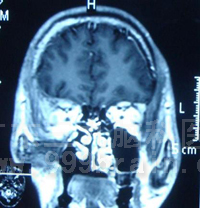

治疗后肿瘤消失。